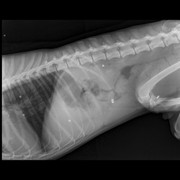

Еще одна свежая история спасения собаки из Сосновки. В субботу, 14 марта, мне позвонили из Сосновки, и сказали, что около магазина лежит собака, у которого болтается лапа и торчит кость.

В понедельник Пал Палыч, известный доктор из Лиды, сделав рентген и взяв анализы, ужаснулся, как пес остался жив. В него стреляли как в мишень. Дробь во всем теле. А лапу перебили палкой, либо каким то тяжёлым предметом.

Сейчас Барни, так назвал его Денис,, на лечении чтобы снять воспалительный процесс и нормализовать анализы. Готовят мальчика к операции. Что будет с лапой, удастся ли ее спасти, пока неизвестно.

Денис будет писать заявление в РОВД по поводу расстрела собаки. Охотников в Сосновке нет. Модет иметь место не зарегистриванное орудие или пнематика.